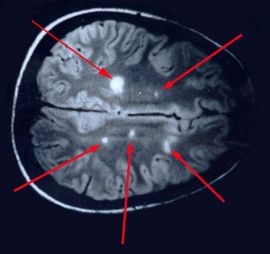

Uns wurde ein englischsprachiger Fachartikel („Multiple sclerosis is Lyme disease: Anatomy of a cover-up„) zugespielt, der an Brisanz kaum zu überbieten ist. Dieser Artikel erklärt, dass der wahre Grund für die Multiple Sklerose (MS) eine Infektion mit Borrelien-Erregern (Bb s.l., Borrelia burgdorferi) ist. Minutiös wird hier aufgelistet, dass diese Tatsache eigentlich schon seit 1911 bekannt ist und immer wieder von unabhängigen Studien weltweit bestätigt wurde. Aber diese Ergebnisse wurden scheinbar systematisch vom medizinisch-industriellen Komplex unterdrückt und stattdessen die Forschung in andere Richtungen gelenkt, wo sie bis heute ja keine Resultate zu verzeichnen hat. MS sei nur ein Symptom der Lyme Borreliose! Im Gehirn jedes MS-Patienten seien nämlich Lyme-Spirochäten Erreger gefunden worden.

Lyme-Multiple-sclerosis Bildquelle: owndoc.com